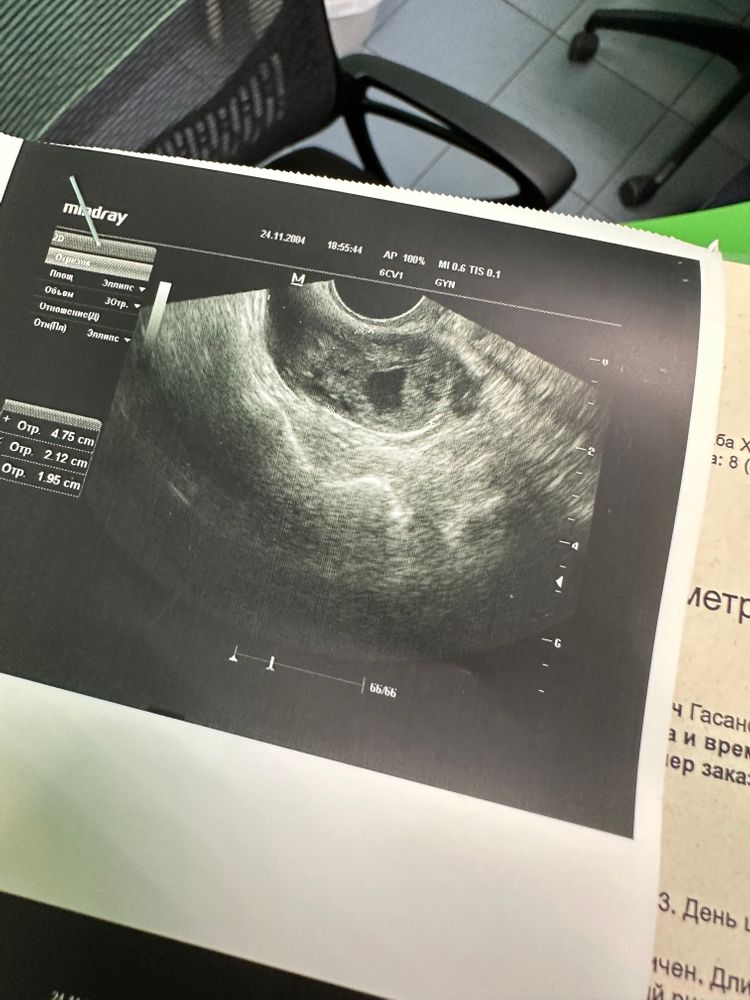

Представляете была еще одна Овуляция 🙏🏻, этого «уродца» не перепутать.

И Овуляция была 6-7 дней назад в том яичнике, где есть труба